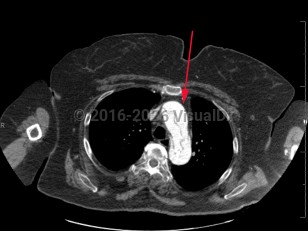

Chest pain, Dyspnea, 50-59 year old Female

PneumomediastinumPneumomediastinum